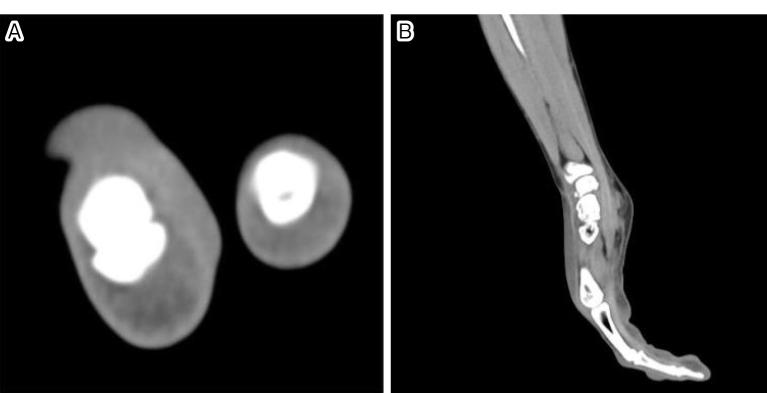

Necrotizing fasciitis is a rare, severe, life-threatening, and rapidly progressing infection characterized by necrosis of the fascia and subcutaneous tissue with systemic toxicity. In this study, we report a male patient with only controlled hypertension who was diagnosed with necrotizing fasciitis of his middle finger after sustaining a kitchen knife injury. Successful treatment involved amputating the third finger at the level of the medial proximal phalanx due to the severe and rapid progression of symptoms and the elevated risk of . and . causing necrotizing fasciitis, considering the patient's profession as a cook and his being immunocompetent. The patient was able to resume a working life after a short hospitalization without any severe complications. This is a reminder that even a minor injury can result in a life-threatening infection. Early surgical intervention saved the patient's life, eliminated the need for reoperation, and shortened the hospitalization.

坏死性筋膜炎是一种罕见、严重、危及生命且进展迅速的感染性疾病,其特征为筋膜和皮下组织坏死并伴有全身毒性。在本研究中,我们报告了一名仅患有控制良好的高血压的男性患者,他在遭受菜刀切割伤后被诊断为中指坏死性筋膜炎。鉴于症状严重且进展迅速,以及考虑到患者厨师的职业和免疫功能正常,坏死性筋膜炎导致……和……的风险升高,成功的治疗措施是在近节指骨中部水平截除第三指。患者在短期住院后能够恢复工作生活,未出现任何严重并发症。这提醒我们,即使是轻微损伤也可能导致危及生命的感染。早期手术干预挽救了患者生命,避免了再次手术的需要,并缩短了住院时间。